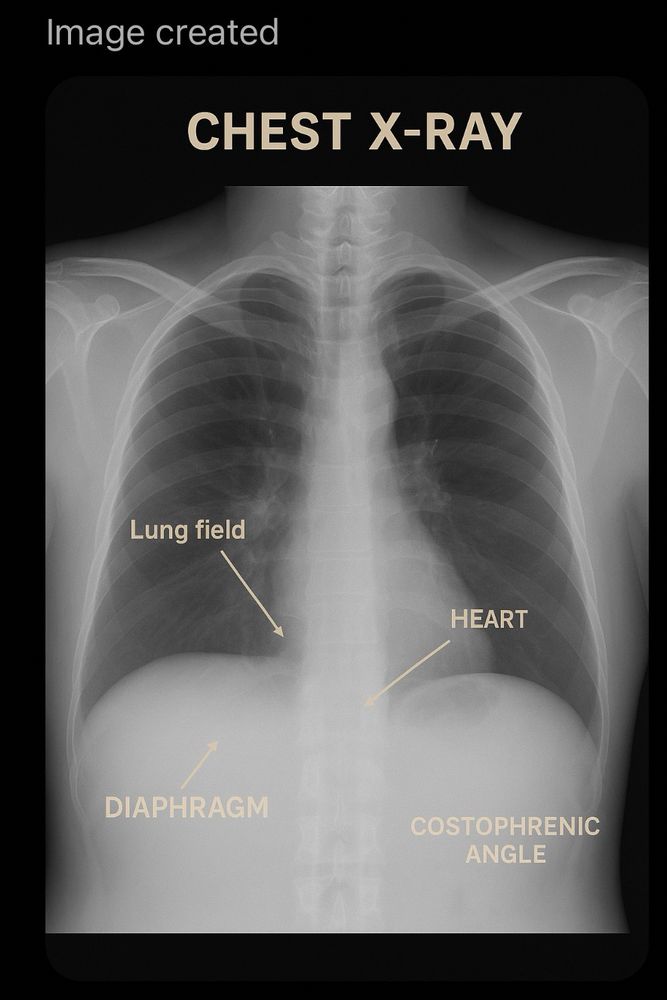

If this is the state of A.I. labelling a chest x-ray on ChatGPT now (it's wrong), I can't imagine radiologists will lose their jobs to machines reporting prostates anytime soon.... Where the Labour party think AI can do this really beggars belief!